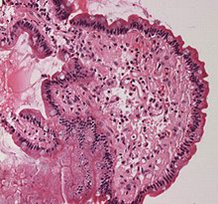

类淀粉蛋白

一种不可溶的纤维性蛋白质

在器官中不正常的堆积,会造成类淀粉沉积症

类淀粉沉积症

神经系统中出现大量的淀粉样物质的累积沉淀